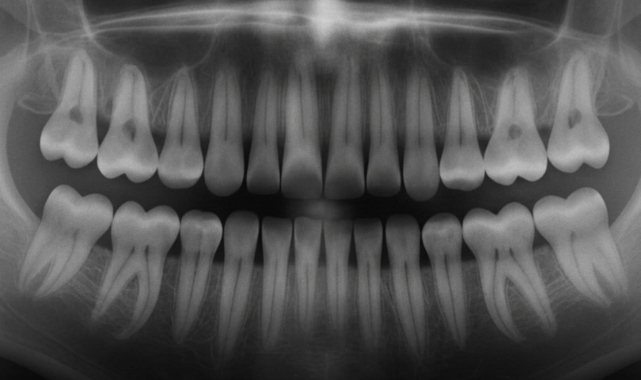

Japonya’da bilim insanları, diş kaybı ve çürük sorunlarına devrim niteliğinde bir çözüm sunabilecek yeni bir ilaç üzerinde çalışıyor. Deneme aşamasındaki bu tedavi, insan dişlerinin yeniden büyümesini teşvik ederek protez ve implantlara olan ihtiyacı ortadan kaldırmayı hedefliyor.

Erken çalışmalar, ilacın doğal diş rejenerasyonunu desteklediğini ve milyonlarca kişinin diş kaybı veya çürük sorunlarından kurtulmasına umut verdiğini gösteriyor. Geleneksel diş tedavilerinin aksine, bu yaklaşım vücudun kendi iyileşme mekanizmalarıyla çalışıyor, invaziv işlemleri ve sürekli bakım gereksinimini azaltıyor.Uzmanlar, tedavinin başarıyla uygulanması halinde ağız sağlığında devrim yaratabileceğini ve diş kaybını geçmişte bırakabileceğini belirtiyor. Diş eksikliği yaşayanlar için bu yenilik, sadece heyecan verici değil, hayat değiştiren bir gelişme olarak değerlendiriliyor. Japonya’nın öncülüğünde yapılan bu çalışmalar, diş hekimliği ve insan sağlığı alanında yeni bir dönemin kapılarını aralıyor.